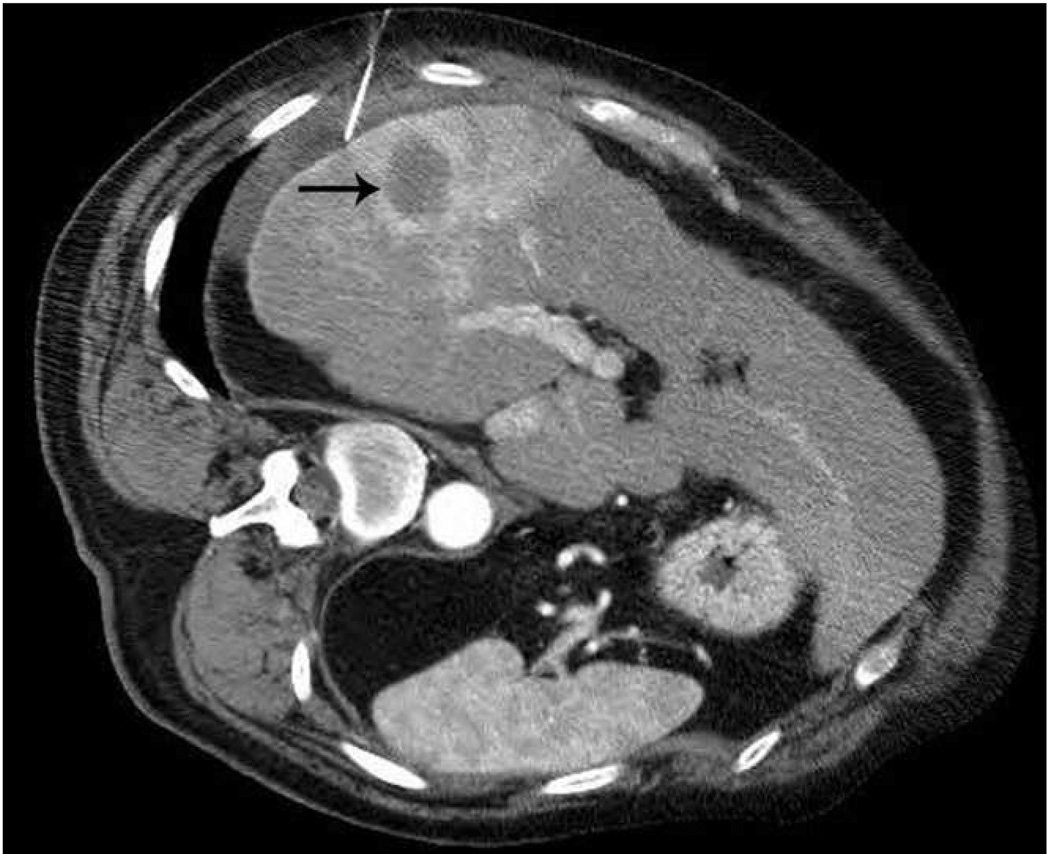

The liver is a vascular solid organ with an abundance of large vessels creating the potential for heat sink effects (Figure 5). Microwaves appear to be more apt to overcome perfusion and large heat sinks than other heat based ablation modalities (5, 10, 48–50). Microwave energy has been shown to ablate tissue up to and around large hepatic vessels measuring up to 10 mm and creates larger zones of ablation in high perfusion areas (5, 49–50). High perfusion rates in hepatic vessels greater than 3 mm limits the effectiveness of radiofrequency ablation, and has been shown to be an independent predictor of incomplete tumor destruction (51).

Figure 5.

Recurrence along a hepatic vein following RF ablation. Pretreatment CT image (a) demonstrates a small low attenuation lesion located between hepatic venous branches (arrow) concerning for metastatic disease in this patient with colorectal cancer. US image during treatment with RF ablation (b) demonstrates gas encompassing the small lesion. Follow up CT (c) demonstrates a low attenuation ablation zone (A) with local tumor progression along the margin abutting the hepatic vein (arrow).